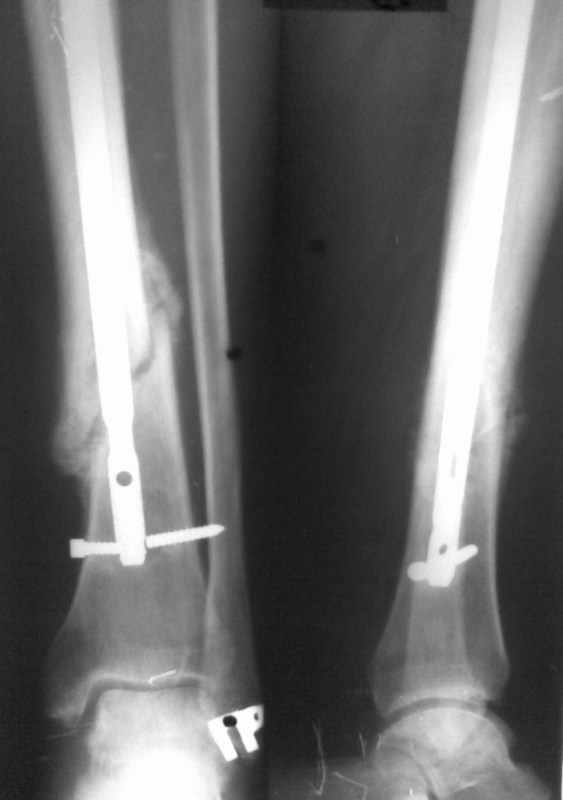

Сломан дистальный блокирующий винт Больному произведено ОМС перелома голени блокирующим стежнем 2 мес. назад. Через 1 мес больной начал наступать на ногу. В результате такая картина. Удален сломаный конец винта.Интересует вопрос о дальнейшей тактике лечения. Кто может посоветовать как дальше поступить. Оставить все как есть и приступать на ногу, провести замену стержня на другой или поступить как-то иначе. Спасибо за советы и предложения

снимки в приложении

Мое мнение - есть хорошая мозоль, и ось конечности весьма неплоха. Я бы оставил все как есть и рекомендовал бы больному на всякий случай повременить с нагрузкой на ногу еще на пару месяцев .

Конечно, изначально было бы лучше гвоздь взять на 2-4 см длиннее ( скорее на 4) и заблокировать его 2-3 шурупами, но, что сделано - то сделано